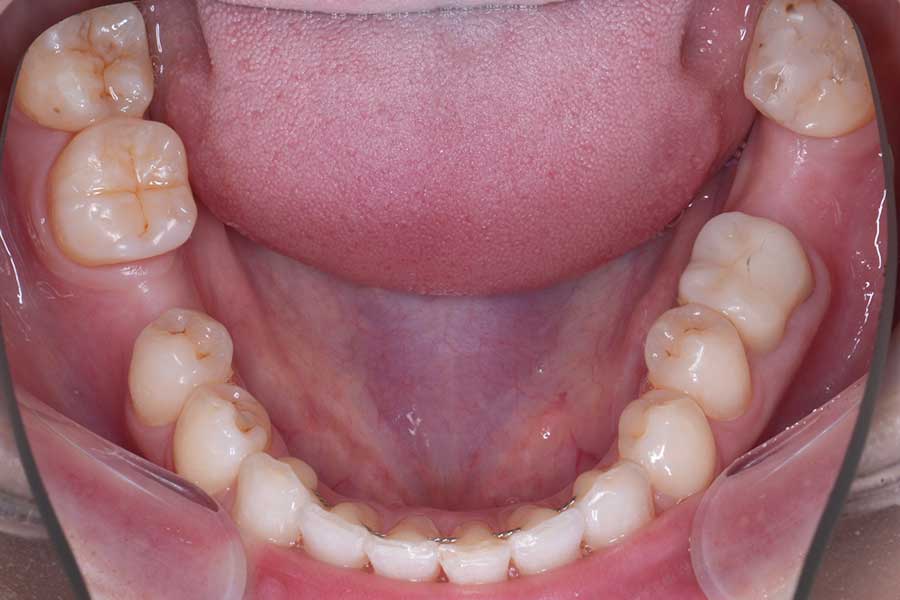

治療前

主訴 インプラント治療前にブラックトライアングルを消したい

治療内容 上下顎ラビアル矯正(表側矯正)